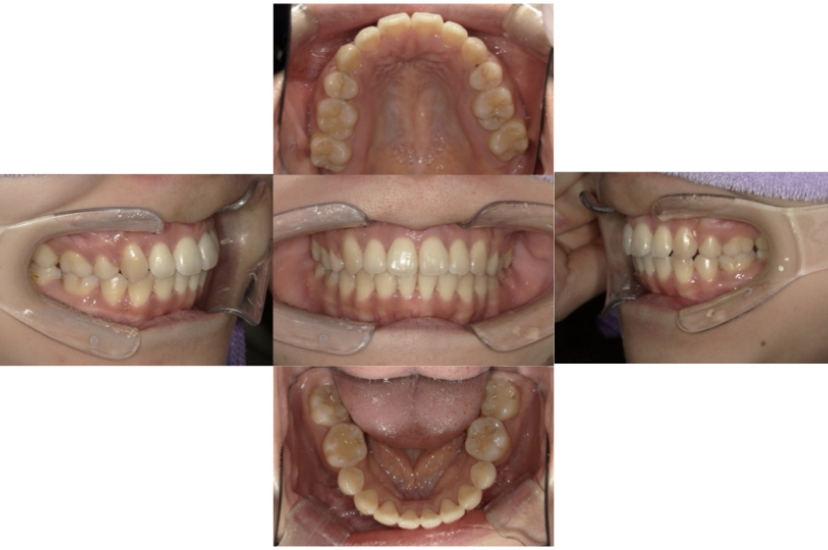

BEFORE

AFTER

上下顎叢生(上下の前歯のガタガタ)のケースです。

装置はラビアル(上下表側)で、上下顎の小臼歯を4本抜歯を行っています。抜歯したスペースを利用し、上下の前歯の後方移動と叢生(ガタガタ)の改善を行っています。歯科用アンカースクリューを使用することで、可能な限り前歯を後方移動させています。

主訴 上下の前歯のガタガタで歯が磨きづらい。

年齢・性別 16歳 男性

治療方針 抜歯スペースを利用して上下前歯の叢生(ガタガタ)の改善

抜歯部位 上下顎左右第一小臼歯

使用装置 ラビアル(上下表側)、顎間ゴム、歯科用アンカースクリュー

治療期間 2年3か月

治療回数 24回